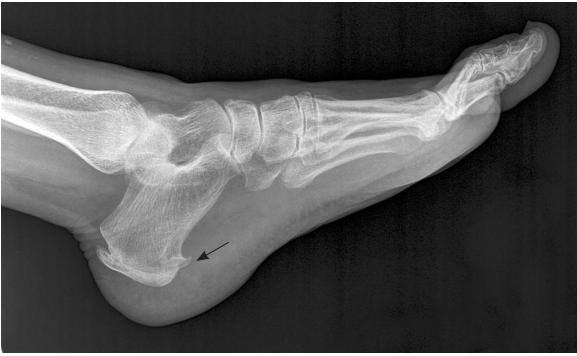

如果去医院拍片子,可能会发现如下图一般的跟骨骨刺(黑箭头所示)。

并不是因为长骨刺,才得了足底筋膜炎。因为很多没有任何症状的人也会有这里的骨刺,而很多有足底筋膜炎的患者并没有跟骨骨刺。所以无论是疾病病因,还是后面的治疗,都跟这个骨刺没多大关系。哪些告诉你说能消骨刺治这个病的,别信就好。